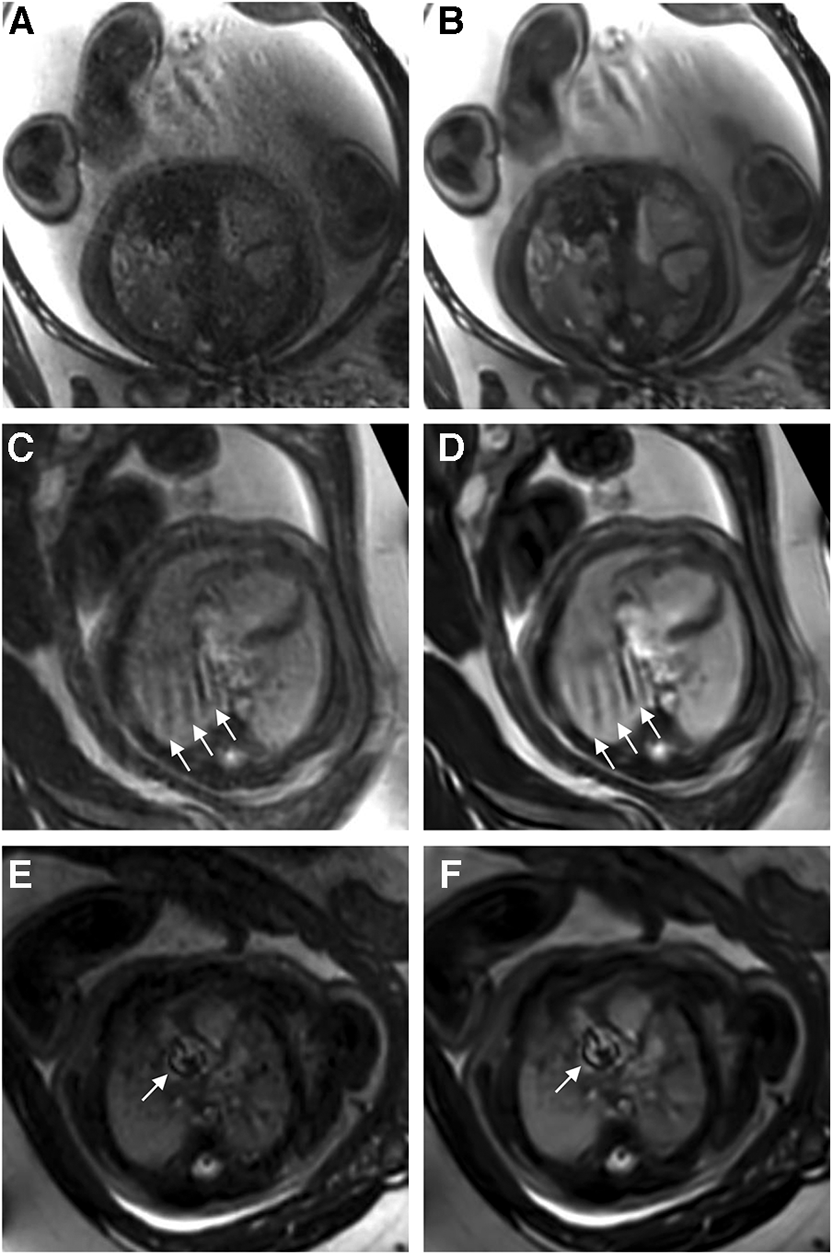

Reader 1 rated the bSSFP DL cine as significantly better for image contrast [3 (2–4) vs. 5 (4–5), P < 0.001] and endocardial edge definition [3 (2–4) vs. 4 (4–5), P < 0.001]. Regarding artifacts, CS and DL reconstructions scored equally [4 (3–4.75) vs. 4 (3–4), P = 0.4] (see Table 2 for quality ratings by reader 2). Intra- and inter-observer reproducibility was good or excellent for rating image contrast and endocardial edge definition, whereas the intraclass correlation coefficient was moderate or good for reproducibility regarding artifacts (see Table 3). Minor artifacts occurred in all 23 fetuses (e.g., motion artifacts), which did not hinder the diagnostic assessment of cardiovascular structures. New artifacts related to the DL reconstruction were not noted. Examples of image artifacts are provided in Figure 3.

Figure 3

(A,C,E) Standard CS and corresponding (B,D,F) DL image reconstructions of an axial balanced steady-state free precession cine sequence affected by different types of artifacts, including dielectric effects (A,B), maternal breathing (arrows in C,D), and arterial pulsation (arrows in E and F). No attenuation of artifacts was noticed by using the DL denoising algorithm for image reconstruction compared to the standard images. In fact, the pulsation artifacts in (F) caused by aortic valve stenosis seem even more pronounced compared to the corresponding standard image (E); the complete axial cine imaging stacks of both the standard CS reconstructions (Supplementary Movie S1) and the DL reconstructions (Supplementary Movie S2) are provided.